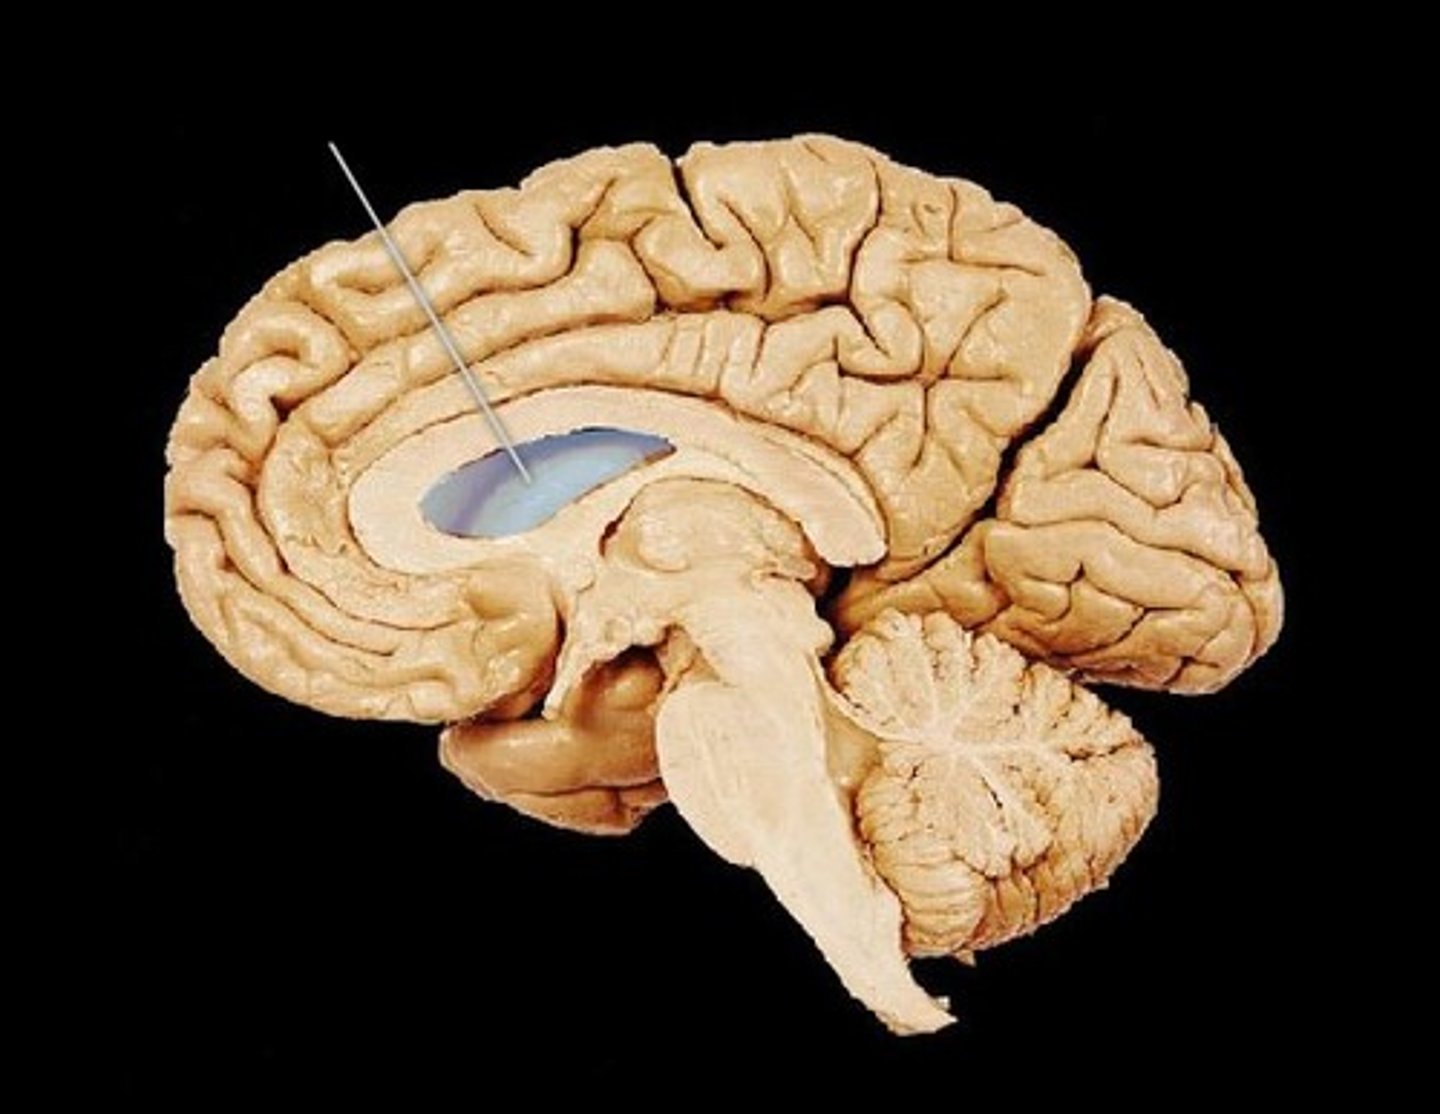

cerebrum

Largest part of the brain; responsible for voluntary muscular activity, vision, speech, taste, hearing, thought, and memory.

Diencephalon

thalamus, hypothalamus, epithalamus

thalamus

the brain's sensory switchboard, located on top of the brainstem; it directs messages to the sensory receiving areas in the cortex and transmits replies to the cerebellum and medulla

hypothalamus

A neural structure lying below the thalamus; it directs several maintenance activities (eating, drinking, body temperature), helps govern the endocrine system via the pituitary gland, and is linked to emotion and reward.

epithalamus

Contains pineal body. Involved in olfactory senses and sleep/wake cycle- melatonin

cerebrospinal fluid (CSF)

plasma-like clear fluid circulating in and around the brain and spinal cord

CSF circulates through

lateral ventricles to third ventricle to cerebral aqueduct to fourth ventricle to subarachnoid space and central canal of spinal cord

lateral ventricle

one of the two ventricles located in the center of the telencephalon

third ventricle

the ventricle located in the center of the diencephalon

cerebral aqueduct

connects the third and fourth ventricles

fourth ventricle

the ventricle located between the cerebellum and the dorsal pons, in the center of the metencephalon